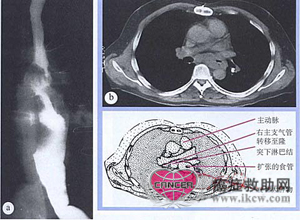

鳞状细胞癌。60岁男性患者,伴进行性吞咽困难和体重明显下降。内镜检查见食管中1/3段肿瘤。(a)钡餐显影见食管狭窄,伴粘膜破坏,符合食管癌。(b)CT扫描显示局部转移和原发大肿瘤堵塞食管。联合放化疗3个月后,达到完全临床缓解。不幸的是随后发生了肝转移。